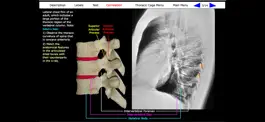

Gross anatomy is defined as the study of anatomy with the unaided eye, essentially visual observation without the use of significant magnifying technologies. This application describes the gross anatomy of the human bones, which when assembled create the structural framework of the body called the skeleton. The gross anatomy of human bones is typically studied by viewing the distinctive features of "dried" bones. A dried bone is one in which the soft tissues, i.e. the organic components of the bone, have been removed, leaving only the hard, inorganic, mineralized framework of the bone. Indeed, the term "skeleton" is derived from the Greek meaning "a dried body, mummy" (Dorland's Medical Dictionary). This application includes 139 images of dried human bones that collectively address the entire human skeleton. Unlike many other applications, these are real bones, not computer simulations of bones. The images are derived from the bone collection of The George Washington University School of Medicine and Health Sciences in Washington, D.C.

The content is organized into six body regions, which are accessed from the Main Menu. Each bone image has a Description, a Test, and a Labels button. Many bone images have an accompanying Correlation image.

Correlation: Many of the bone images have an accompanying Correlation image. The Correlation image is designed to relate the gross anatomical features of the bone with their appearance in another visual medium, such as an x-ray. This feature is particularly valuable to users with an interest in the clinical sciences.